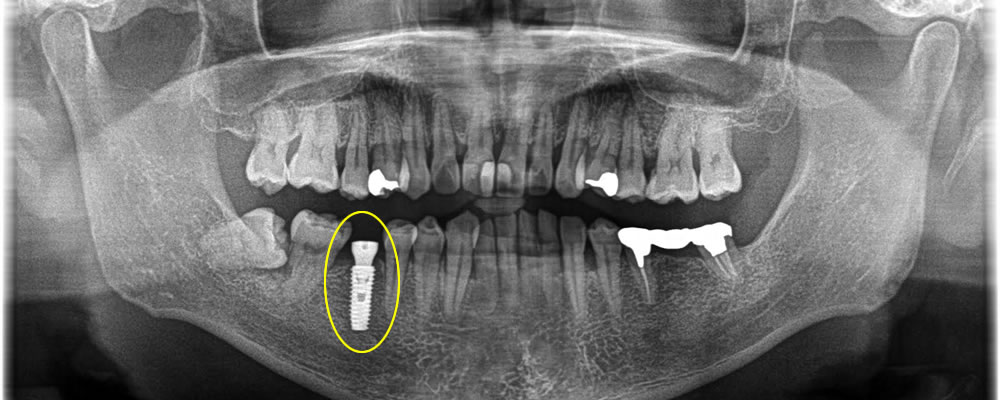

インプラント治療完了後のレントゲン・口腔内写真

次に歯の色を白くしていきたいとの事で、ホワイトニングを2回行い、満足いく色になったタイミングで前後の歯にジルコニアインレーを作成しました。

その後インプラントがしっかりとくっついているのを確認し、上部にジルコニアの歯を作成しました。

結果、色合いも綺麗になり、満足して頂く事ができました。